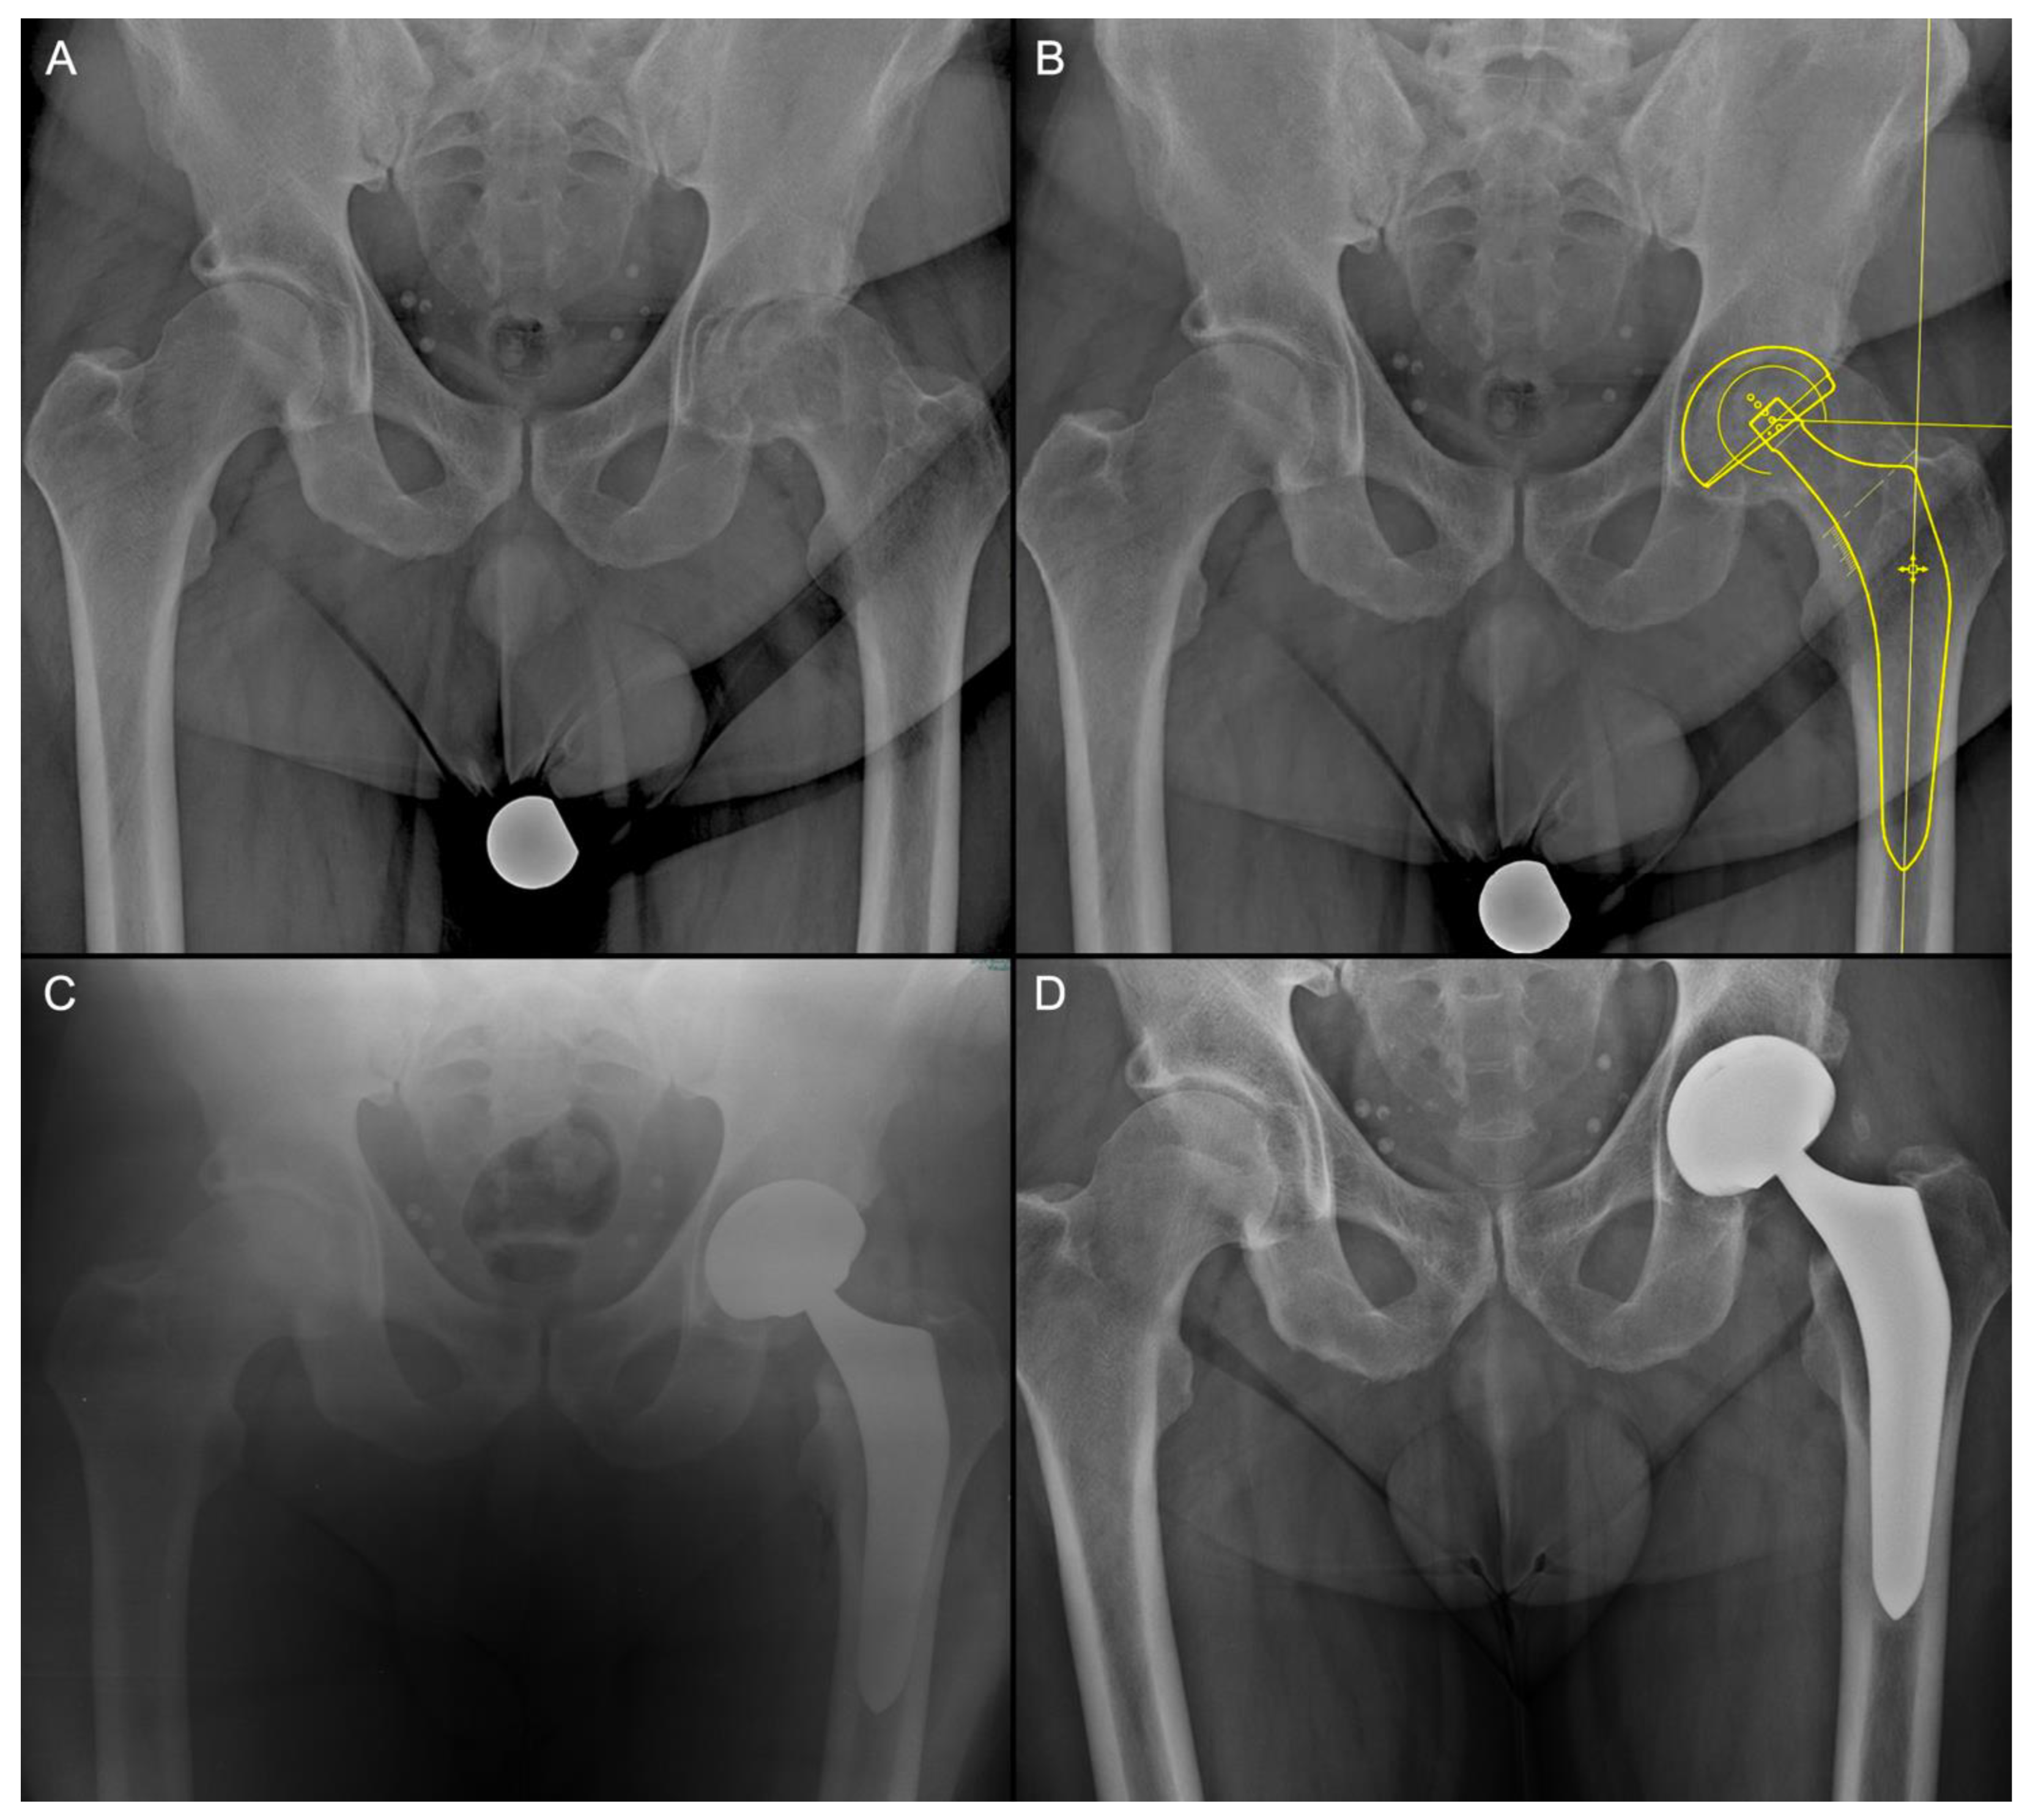

2.2. Surgical Technique

2.4. Clinical and Radiological Evaluation